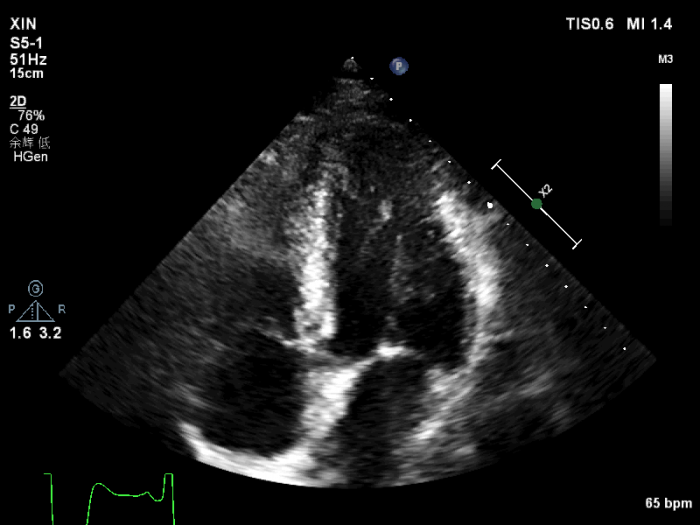

经胸超声心动图提示,心尖四腔心:心尖部心肌及心内膜显示模糊不清。